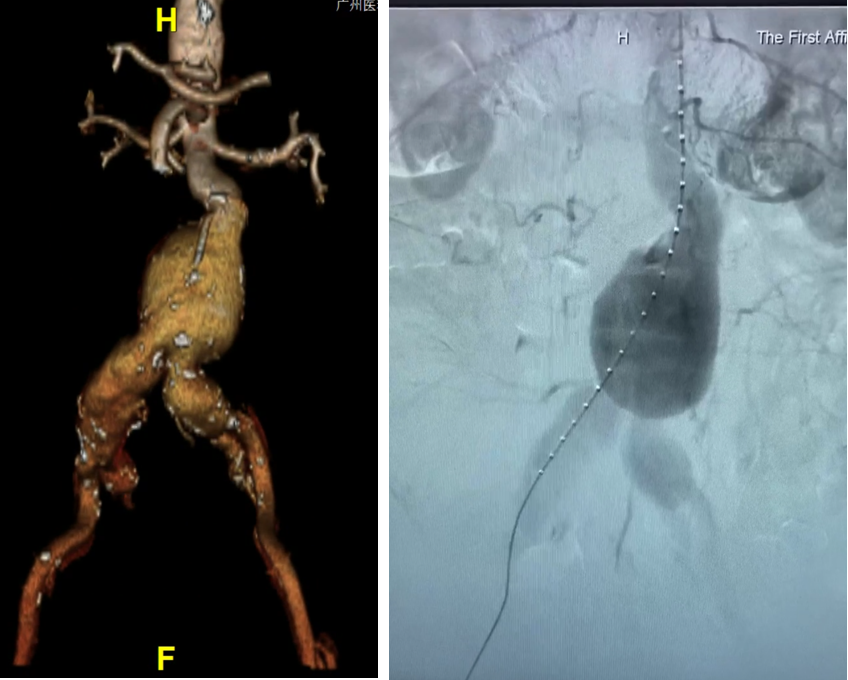

病例1

75岁女性 ,AAA合并双侧髂总动脉瘤 ,首次EVAR术后出现内漏 ,采用G-iliac™IBD成功重建右侧IIA ,术后造影效果良好。

左图:EVAR术后;右图:选用IB-1610-080-150,在髂内开口20mm处打开

肱动脉超选髂内,植入PS-C-10080XL,充分后扩

术后造影,效果良好,成功保留髂内动脉

68岁男性 ,因腹主动脉瘤及双侧髂总动脉瘤入院。左侧采用商品化IBE支架、右侧行栓塞。术中利用牵引导丝快速超选髂内完成重建 ,右侧引入腹主主体 ,通过喇叭腿与IBE衔接 ,造影隔绝瘤腔 ,术后1月随访显示瘤体隔绝良好 ,左侧髂外分支通畅。

左侧IBE+右侧栓塞

利用牵张导丝,快速超选髂内,完成髂内重建

右侧引入腹主主体,喇叭腿与IBE桥接。造影隔绝

术后1月随访,整体隔绝,左侧髂内外分支通畅